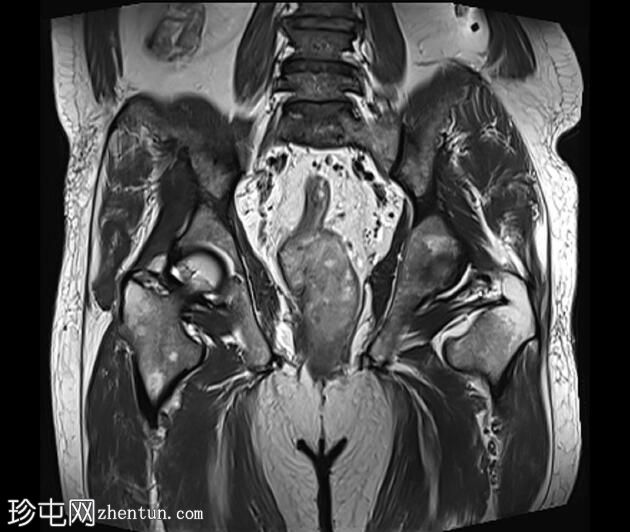

冠状位

T1加权像

可见一不规则分叶状肿块,累及直肠中段和远端,头尾方向长约7 cm,下缘距肛缘约2.5 cm。在T1加权像和T2加权像上,该病灶相对于骨骼肌均呈高信号。 PDFS(脂肪抑制)图像显示持续高信号强度,提示存在黑色素和/或出血成分。

增强扫描显示病灶内呈不均匀强化。直肠下段7点钟位置的系膜筋膜受累。后方系膜可见少量淋巴结。未见邻近器官侵犯。